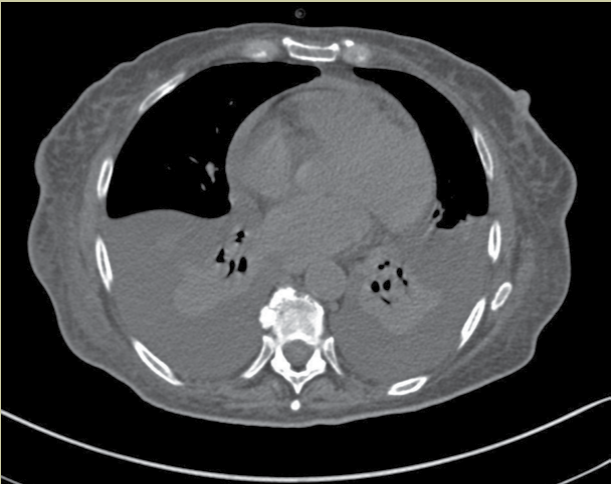

Mujer de 66 años que ingresa al servicio de urgencias con dolor torácico tipo opresivo y disnea. A la exploración física, la paciente reportó taquipnea y saturación de oxígeno (SatO2) de 78% al aire ambiente.

1. ¿Cuál es el método de estudio que muestran estas imágenes?

2. ¿Cuál es la ventana usada en este estudio para valorar al pericardio?

3. En los cortes y reconstrucción mostrada, ¿qué patología podemos observar en el pericardio?

4. Además de la patología pericárdica, ¿qué otro hallazgo se identifica en estas imágenes?

a) Derrame pleural

Respuestas: 1: d); 2: b); 3: d); 4: a); 4: a).